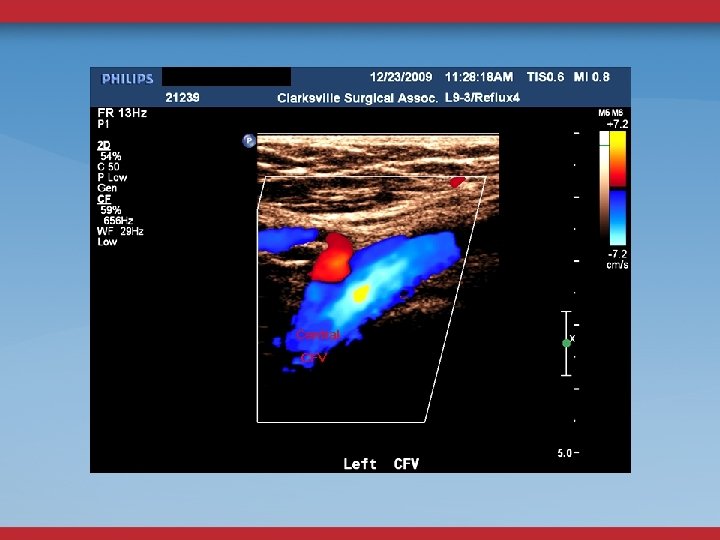

LE VENOUS DUPLEX US REFLUX OBSTRUCTION CFV DOPPLER FLOW CONTINUOUS? ASYMMETRY? FEMORAL VEIN COLLATERALS

ABDOMINAL/PELVIC DUPLEX FLOW AND ANATOMY STENOSIS MINOR DIAMETER REDUCTION ELEVATED PEAK VENOUS VELOCITY RATIO >2. 5 FLOW REVERSAL GONADAL, ASCENDING LUMBAR, PELVIC VARICOSITIES